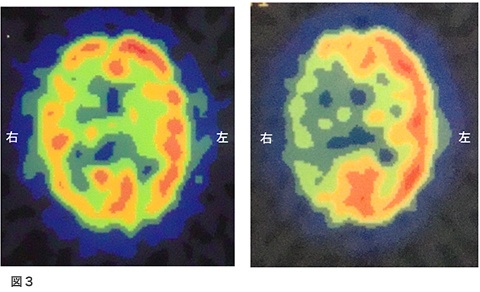

脳梗塞で発症された方です。意識障害と左不全片麻痺、構音障害で発症されました。図1が入院時のMRI拡散強調画像です。右側の白くなっているところが脳梗塞になっている部位です。図2の、MRA(MRIで行う血管の検査)では、右側の中大脳動脈の描出がほとんど無い状態でした。

脳血流検査(SPECT)図3

左は、安静時検査、右がダイアモックス負荷時の検査です。安静時で右側の血流が低下していますが、ダイアモックスの負荷でさらに左右差が拡大しています。これは、盗血現象と呼ばれ脳循環予備能の強い障害を示します。